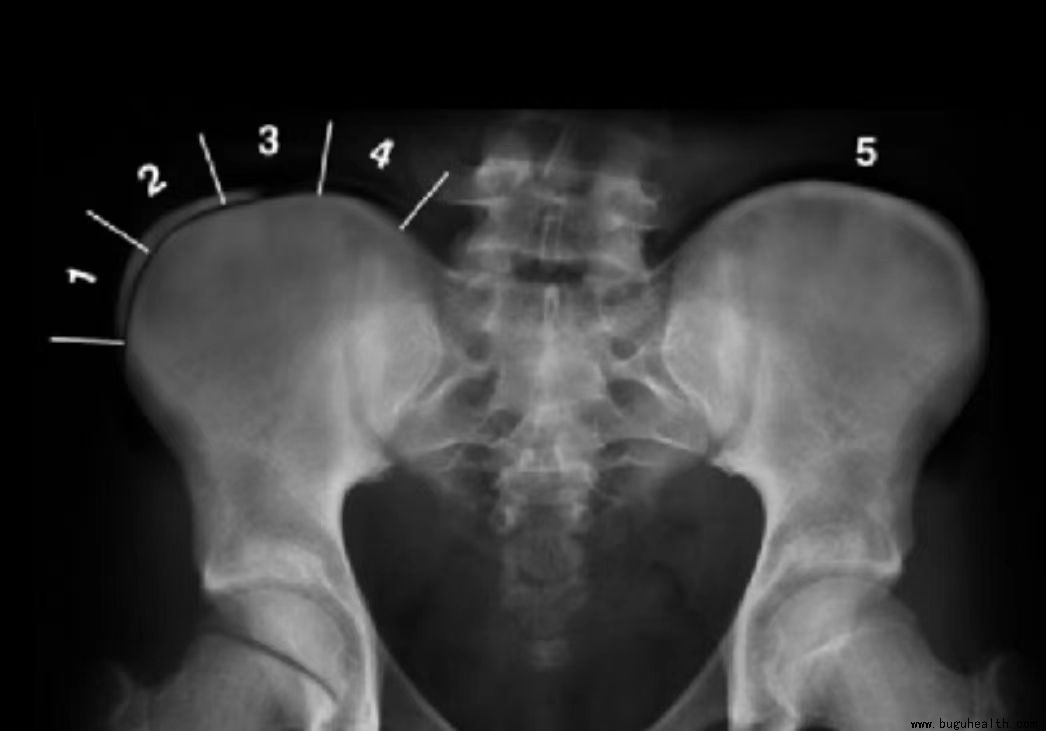

一、髂骨上方骨骺线闭合程度判断侧弯恶化风险: risser指数数越小,脊柱侧弯的恶化风险也就越大。

二、Cobb角测量:

< 15 °,轻微脊柱侧弯,无椎体旋转:运动治疗与定期观察X片: 三个月到半年

15° -20°,伴有椎体旋转:针对性脊椎侧弯矫正运动,还在增需配戴支具

20°-40°,恶化中的脊柱侧弯:支具+侧弯矫正运动+强化锻炼;

> 40°-50° ,⼿术治疗:所有保守疗法皆失效。

综合考虑:cobb角-3×骨龄(Risser指数)